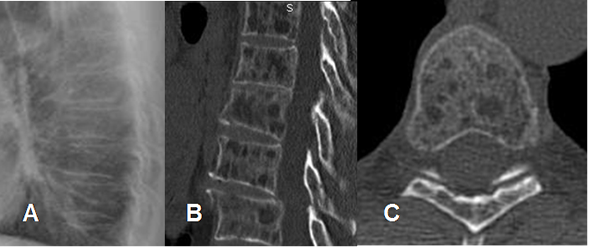

Fig 157. Micrometástasis.

A: Rx lateral. No se encuentran alteraciones.

B: TAC reconstrucción sagital y C: TAC axial. Múltiples lesiones líticas vertebrales, por micrometástasis secundaria a infiltración leucémica.